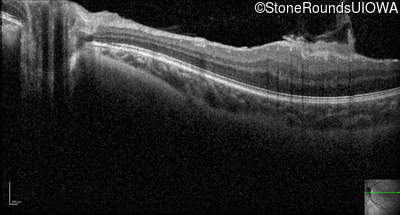

Optical Coherence Tomography - Left - 20/80

Exemplar / OCT Stack